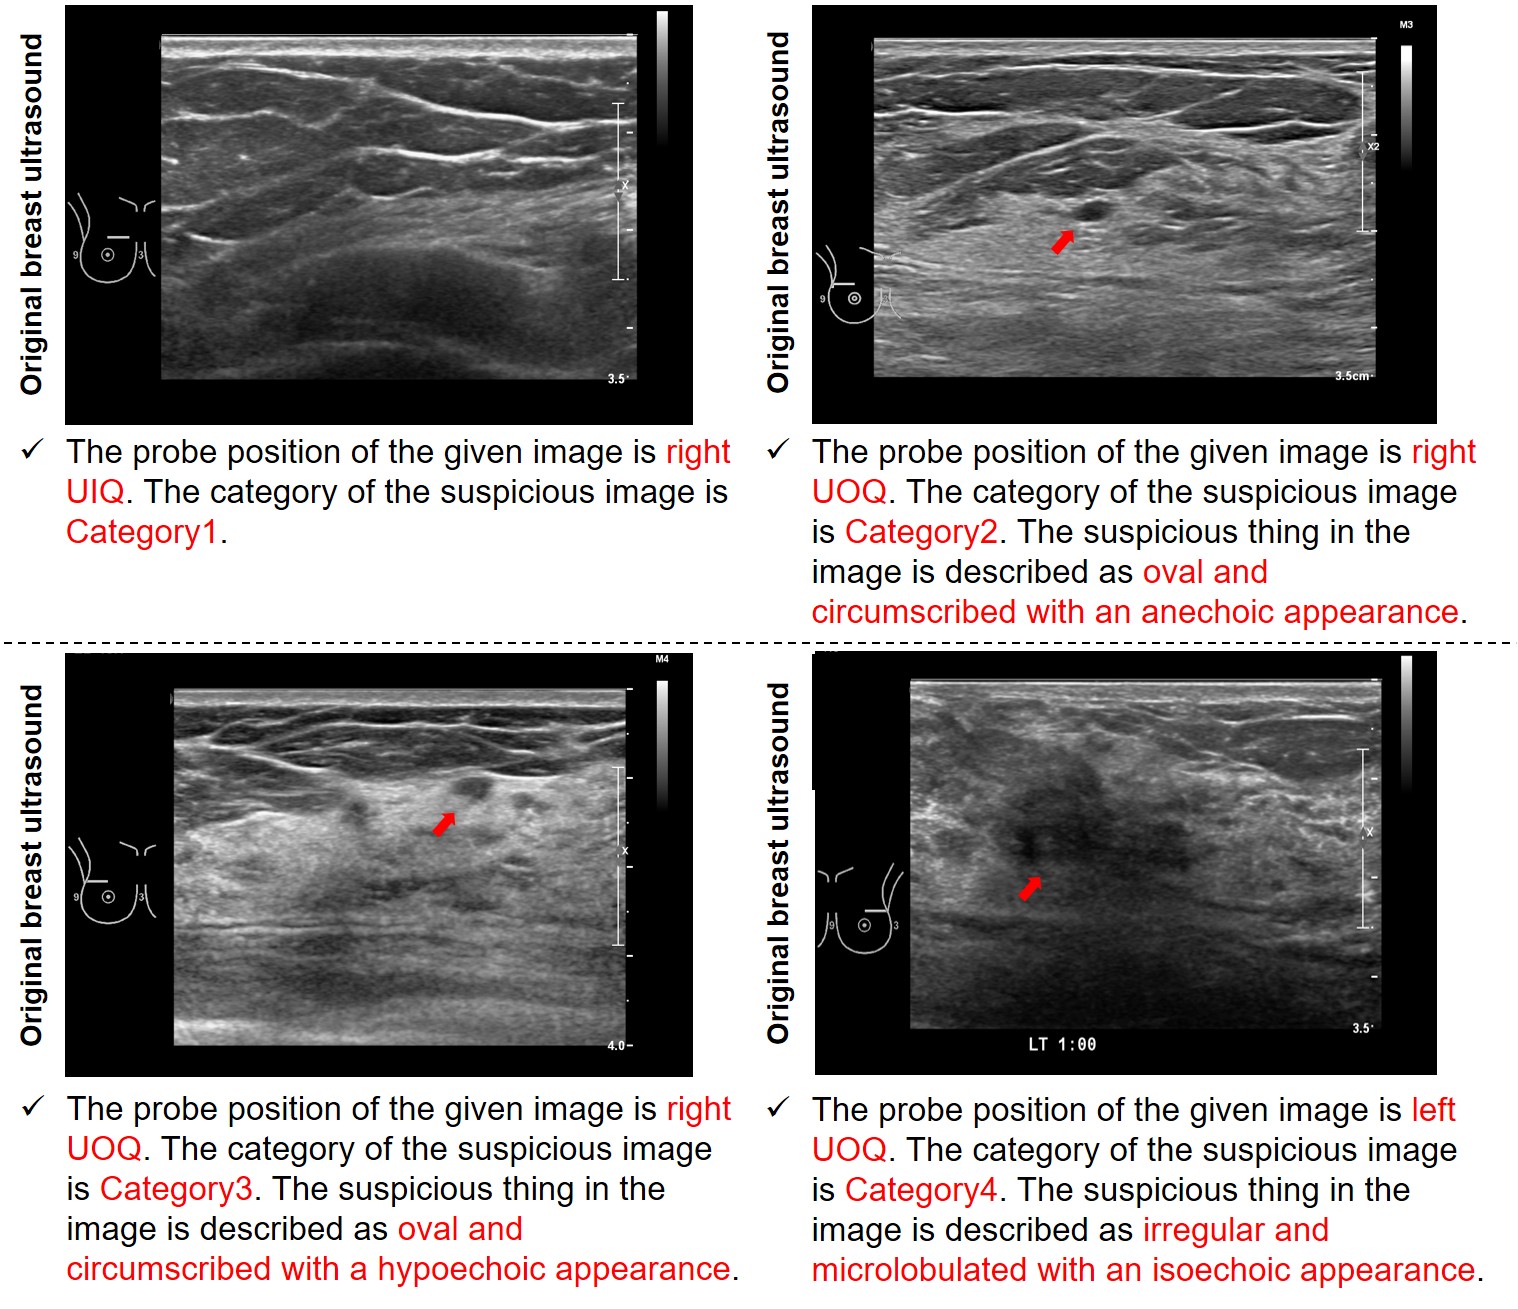

Fig. 6: Representative results of our preliminary report generation. The red denotes the generated information from each designated tools.

The outcomes are presented in Figure 6, where we have included four representative results. The red annotations signify the information generated by each of the tools, encompassing probe information, image category, and details pertaining to shape, margin, and echo. It is evident that the generated preliminary reports effectively encapsulate crucial information corresponding to the respective BUS images.